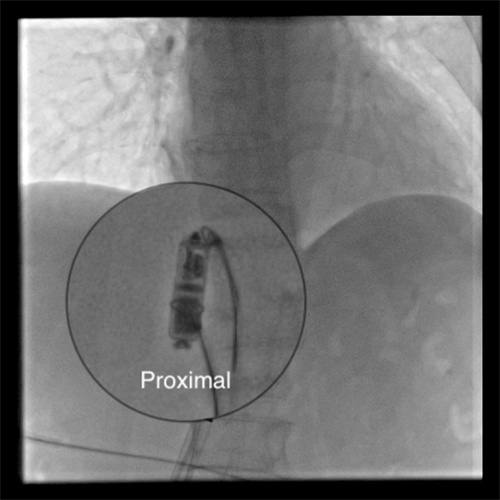

采用单通道双圈套器技术成功捕获到起搏器

近日,湖南省人民医院集团澧县人民医院利用介入技术成功处理了一位八旬老太的罕见“心”事。这位八旬老太因反复出现心慌来到医院。经检查发现是植入的无导线起搏器出现移位,并发频繁地异位起搏,并且脱落的起搏器在心脏里到处乱串,严重威胁到老人生命安全。湖南省人民医院派驻澧县人民医院的颜鹏副院长接手后,率领当地介入血管外科和心内科紧急制定处理方案。在没有可借鉴经验的困难情况下 ,创新性地采用单通道双圈套器技术,仅仅通过腿部米粒大小的穿刺针道,成功取出了这个脱落的起搏器,该患者也得到了顺利救治康复出院。查阅相关文献,这也属于国际上罕见的成功处置案例。